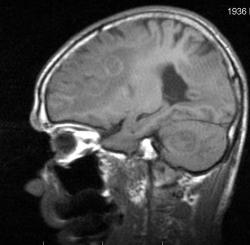

Мужчина 73 лет. За последний год похудел, потерял аппетит. Последний месяц стал плохо ходить, несколько раз падал, неделю назад стал психически не совсем адекватен. Врач - друг семьи, приехавший в гости, настоял на проведении МРТ головного мозга, рентгенографии ОГК и УЗИ брюшной полости. МРТ проводилось в медикаментозном сне, с реанимационным набором наизготовку, по немного укороченным программам. Все закончилось благополучно. Ничего сложного в плане диагностики. Просто не всегда бывает так много и ярко. Есть небольшое продолжение. Потом.

Т1 сагиттальные сканы:

метастазы